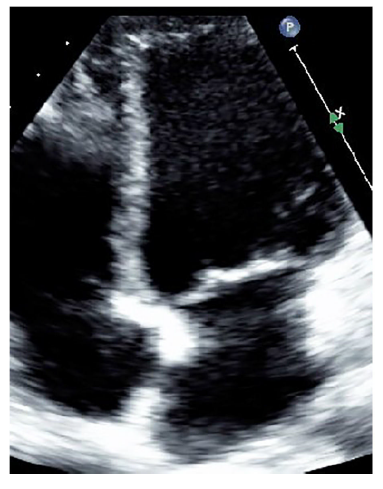

En vista de lo anterior se indicó cirugía cardiovascular de urgencia, en la que se hizo resección de la masa sin complicaciones. El resultado de Patología correspondió a mixoma; en controles posteriores se observó evolución adecuada (fig. 2).